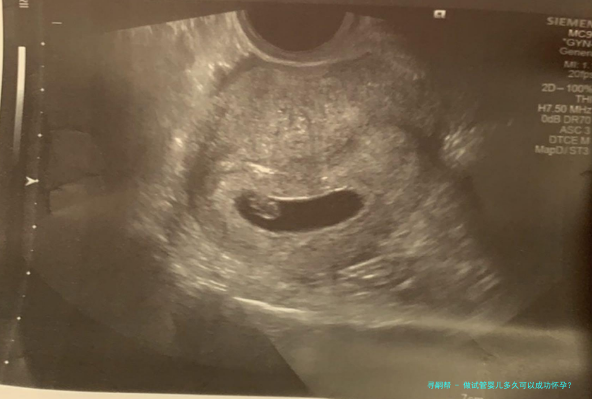

七、确定怀孕

胚胎移入子宫后,通常半个月即可尝试是否怀孕,可先通过早孕试管检查,然后用B超认定。具体检测时间适女性周期确定。确定受孕后要依从医生的嘱咐,定期复查。试管婴儿的怀孕率平常在50%左右,胚胎移植两周后,您就知道妊娠结果了。